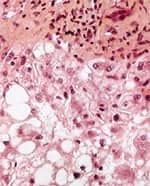

Milk Thistle ExtractIn folk medicine, milk thistle extract (Silybum marianum) traditionally has been used as a liver tonic. It has long been believed that this prickly weed, related to the artichoke, protects the liver against a variety of ailments. In the case of milk thistle, modern science has shown that ancient beliefs about a purported healing herb are based on verifiable fact. Numerous studies have shown that this archaic remedy fights inflammation and enhances the immune system. In fact, silibinin and silymarin—the two flavonoid compounds that serve as the active ingredients in milk thistle extract—are used clinically to treat liver toxicity in Europe and Asia. Studies suggest that in addition to protecting the liver, silymarin and silibinin may also help prevent cancers of the prostate, lungs, and skin, among other organs.85-93 In Vienna, scientists conducted a randomized, double-blind study of silymarin in 170 patients with liver cirrhosis. The patients, more than half of whom suffered from alcoholic cirrhosis, received 140 mg of silymarin three times daily for an average of three and a half years. Silymarin significantly improved the four-year survival rate among cirrhosis patients, including those with alcoholic cirrhosis, in contrast to control subjects who did not receive the herbal supplement. No side effects of silymarin treatment were observed, despite up to four years of continuous treatment.94 Scientists in India recently described the results of a clinical trial in which silymarin reversed markers of liver distress in patients receiving a powerful cocktail of drugs for the treatment of tuberculosis. The drugs are known to increase lipid peroxidation in the liver while depleting glutathione and raising levels of various enzymes associated with liver disease or injury. When elevated, these marker enzymes indicate pathological stress in the liver. When silymarin was administered with the antibiotic drugs, these indicators of liver health improved significantly.95 Charles S. Lieber, MD, a leading researcher in the field of alcoholic liver disease, examined silymarin’s effects on alcohol-induced liver fibrosis in baboons. “Silymarin opposed the alcohol-induced oxidative stress,” in the subjects’ livers, wrote Lieber’s research team. Noting that silymarin significantly slowed the development of alcohol-induced hepatic fibrosis, the researchers emphasized that their findings echo the results of previous studies.”96 Picrorhiza kurroaAnother exotic herb handed down by traditional medicine is Picrorhiza kurroa. A small, increasingly rare perennial herb that grows at high altitudes in the Himalayan region, Picrorhiza kurroa is prized for its liver-protecting properties.97 Picrorhiza has been shown to stimulate liver regeneration in rats, possibly by stimulating nucleic acid and protein synthesis.98 Scientists in India examined the effects of picroliv, the active constituent isolated from Picrorhiza kurroa, on alcohol-induced liver injury in living rats. Although alcohol induced various markers of liver distress, the herb improved all measured parameters of liver health.99 Its mechanism of action and efficacy appear to be similar to that of milk thistle extract, though picroliv may be even more effective than silymarin and silibinin in protecting the liver from toxic insult.97 Another study conducted in India examined picroliv’s effects on the livers of laboratory rats that were exposed to a known carcinogen. The toxin caused predictable effects, including increased lipid peroxidation and depletion of key antioxidants. Levels of antioxidants, including glutathione, were restored to normal in the livers of picroliv-treated rats. Microscopic examination of the animals’ liver tissue showed evidence of severe damage among the control animals, including cell death, inflammation, and growth of cancerous tissue. By contrast, the picroliv-fed rats had virtually normal liver tissue.100 Numerous other studies have investigated picroliv’s liver-protective effects against various toxic and biological insults, including alcohol, hepatitis virus, and various carcinogenic chemicals. All reported a significant protective effect.99-104 Although most studies have involved laboratory animals or cell cultures, human studies have also demonstrated efficacy. For example, in a randomized, double-blind, placebo-controlled trial of patients diagnosed with acute viral hepatitis, Picrorhiza kurroa extract was shown to significantly improve markers of liver health and function in supplemented patients as compared to control subjects.101